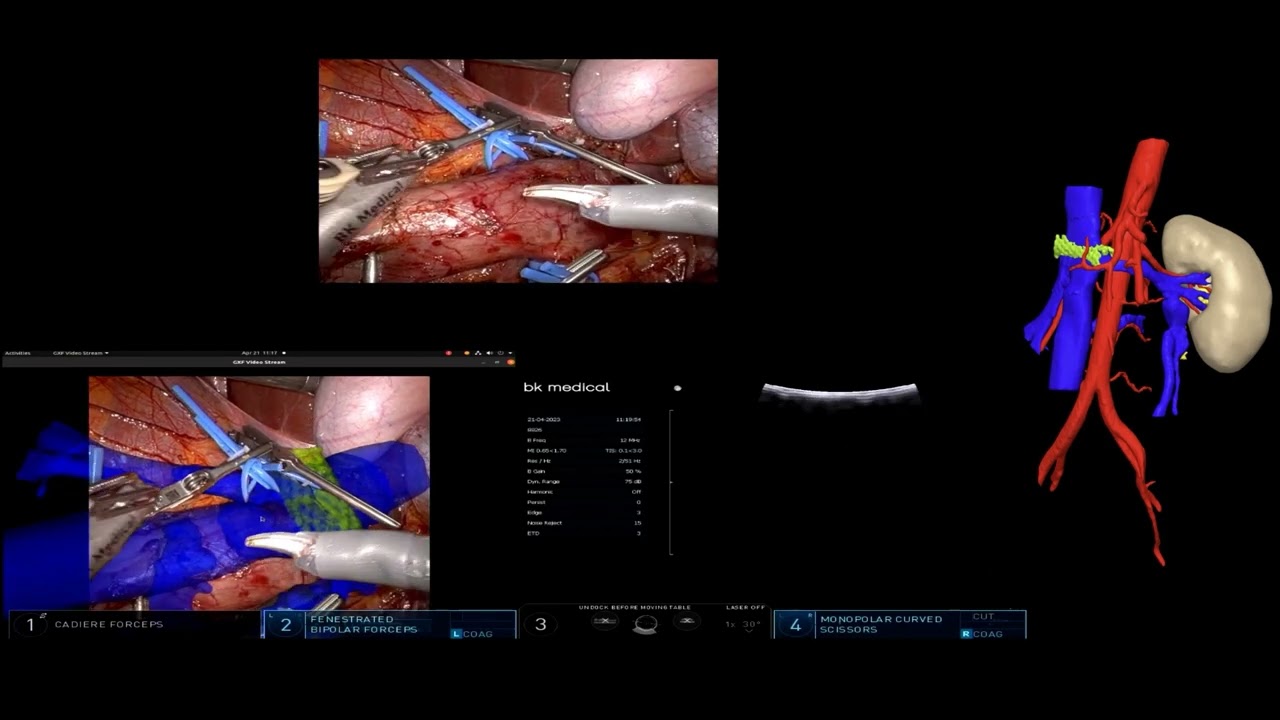

3D Augmented Reality Guided Robotic-Assisted Kidney Transplantation